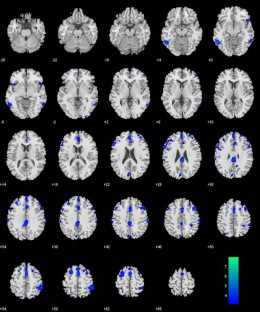

Aging is known to be associated with changes in cerebral morphometry and in regional activations during resting or cognitive challenges. Here, we investigated the effects of age on cerebral gray matter (GM) volumes and fractional amplitude of low-frequency fluctuation (fALFF) of blood oxygenation level-dependent signals in 111 healthy adults, 18–72 years of age. GM volumes were computed using voxel-based morphometry as implemented in Statistical Parametric Mapping, and fALFF maps were computed for task-residuals as described in Zhang and Li (Neuroimage 49:1911–1918, 2010) for individual participants. Across participants, a simple regression against age was performed for GM volumes and fALFF, respectively, with quantity of recent alcohol use as a covariate. At cluster level p < 0.05, corrected for family-wise error of multiple comparisons, GM volumes declined with age in prefrontal/frontal regions, bilateral insula, and left inferior parietal lobule (IPL), suggesting structural vulnerability of these areas to aging. FALFF was negatively correlated with age in the supplementary motor area (SMA), pre-SMA, anterior cingulate cortex, bilateral dorsal lateral prefrontal cortex (DLPFC), right IPL, and posterior cingulate cortex, indicating that spontaneous neural activities in these areas during cognitive performance decrease with age. Notably, these age-related changes overlapped in the prefrontal/frontal regions including the pre-SMA, SMA, and DLPFC. Furthermore, GM volumes and fALFF of the pre-SMA/SMA were negatively correlated with the stop signal reaction time, in accord with our earlier work. Together, these results describe anatomical and functional changes in prefrontal/frontal regions and how these changes are associated with declining inhibitory control during aging.

Fig. 2